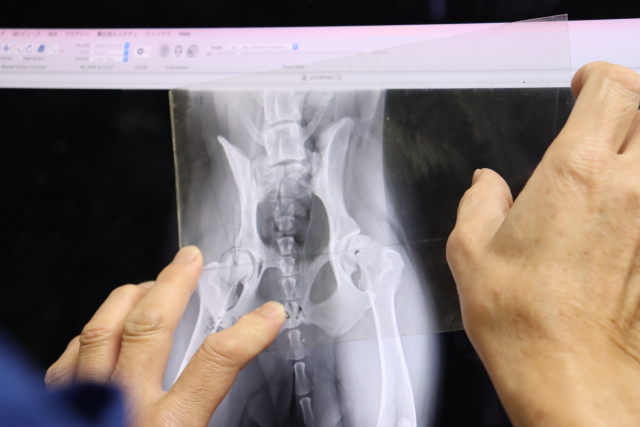

【1】まず麻酔なしで心臓と股関節のレントゲン=心臓大丈夫。

股関節ハマりが浅い。特に左。